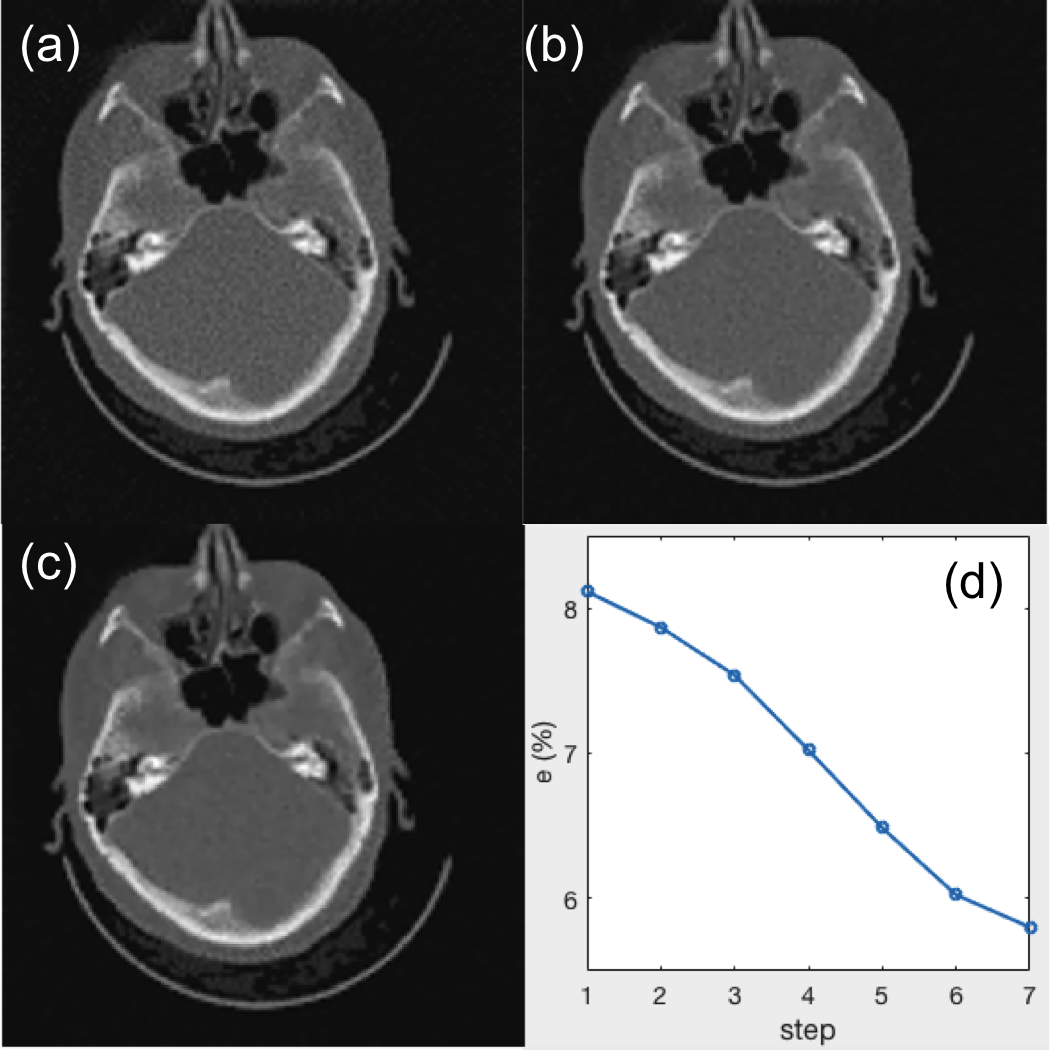

To observe this process in detail, we select a test case that is not used in training. Fig. 5(a)-(c) present reconstructed CT images at step 1, 4, and 7. It is clear that the image quality is improved with the parameter tuned. Quantitatively, we compute the relative error at different steps and plot it in Fig. 5(d). A monotonic decay trend is observed, indicating the effectiveness of parameter tuning.